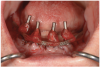

To start, a surgical impression is performed. Open-tray impression copings are secured to the restorative abutments, and a denture-strengthening bar is attached to the copings using a low-expansion pattern resin. The “salt and pepper” technique is used for precise control of the material, thereby avoiding contact with the surgery site and more effectively controlling working time. A plastic impression tray is modified in the occlusal areas where the impression copings will emerge and is tried-in to verify that there are no interferences. Polyvinylsiloxane impression putty is mixed and adapted over the impression copings and denture-strengthening bar. Impression material is also placed in the tray prior to seating. The impression coping screws are exposed and disengaged, allowing the impression to be easily removed. Rigid stabilization of the copings in the impression is verified (Figure 10 through Figure 12). The surgical index is performed using the same provisional prosthesis guide used during the surgery. Only the two anterior implants are indexed. The provisional prosthesis guide is seated to verify the absence of interferences with the two anterior temporary cylinders, and cold-cure acrylic material is applied through the access windows using a “salt and pepper” technique (Figure 13). The prosthesis is held in place with light pressure on the prosthesis guide over the palate or the posterior lingual mandibular ridge until the resin is cured. The VDO is verified after guiding the patient into occlusion with a bite registration recorded in the lab. Esthetic and functional parameters are verified, and the indexed prosthesis is removed with the attached temporary cylinders, and it is then disinfected in cold sterile solution.

Fig 13. Surgical indexing of the two anterior implants—After verifying that the modified provisional prosthesis fully seats without interferences with the temporary cylinders attached to the anterior two implants, cold-cure acrylic material is applied using a “salt and pepper” technique.

Figure 13